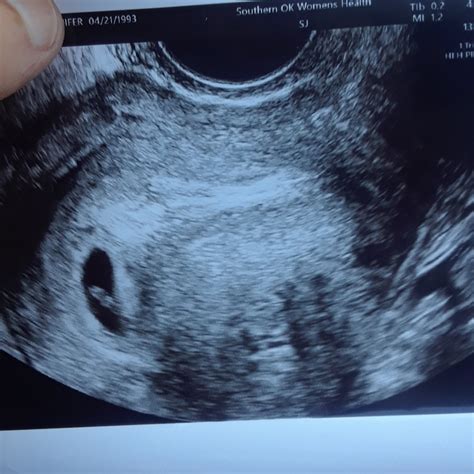

A 5 weeks pregnant sonogram is typically performed transvaginally due to the early stage of pregnancy. This method provides a clearer image of the uterus and the developing embryo. At this stage, the embryo is still very small, measuring about 2 millimeters in length, which is roughly the size of a sesame seed. The sonogram can detect the gestational sac, which is a fluid-filled structure that will eventually house the embryo.

• Results: The technician will capture images of the gestational sac and may be able to see the yolk sac, which provides early nourishment to the embryo.

It's important to note that at 5 weeks, the embryo itself may not be visible on the ultrasound. The primary focus is on confirming the presence of the gestational sac and ensuring that the pregnancy is progressing normally.

• Gestational Sac: A fluid-filled structure that houses the developing embryo.

• Yolk Sac: A small, round structure that provides early nourishment to the embryo.

• Embryo: At 5 weeks, the embryo itself may not be visible, but the gestational sac and yolk sac are important indicators of a healthy pregnancy.